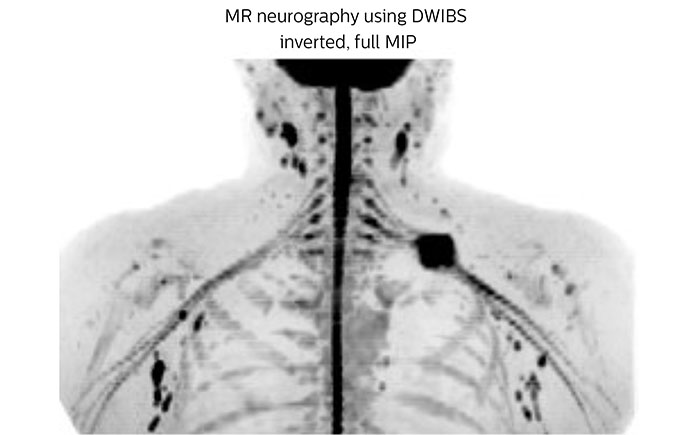

MR neurography of nerve sheath lesion

This patient is a 43-year-old female with a left supraclavicular nerve sheath tumor. The lesion is well visualized on the STIR VISTA images and on the MR neurography using DWIBS. The exam was performed on Prodiva 1.5T.

Acq voxel size 1.2 x 1.3 x 2.4 mm, Recon voxel size 0.7 x 0.7 x 1.2 mm, dS SENSE factor 2, scan time 5:46 min.